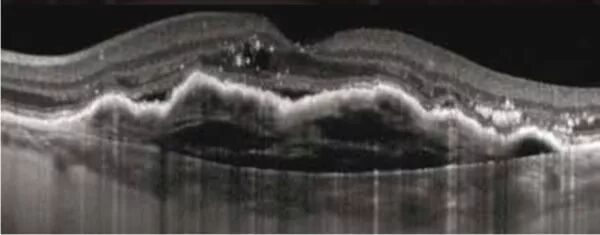

Optical Coherence Tomography (usually referred to by its acronym OCT) is a medical imaging technique that provides cross-sectional images at various depths and reconstructs the entire eye using a principle similar to that of a scanner. It uses non-ionizing infrared radiation and poses no risk.

It can provide images of the retina, optic nerve, cornea, anterior chamber, and iridocorneal angle. OCT is used for the detection of glaucoma, age-related macular degeneration (AMD), and diabetic macular edema.